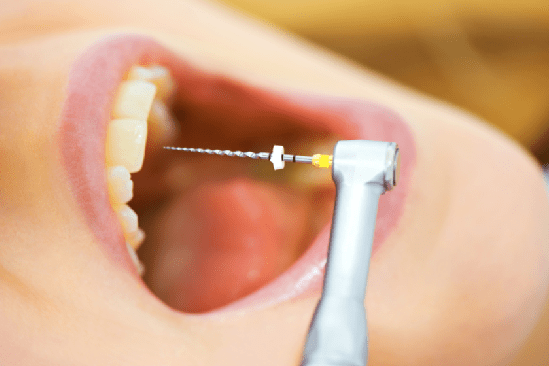

Te informaremos de todas las novedades en tratamientos, técnicas, patologías y consejos para poder disfrutar de una buena salud bucodental y una sonrisa espectacular. Hablaremos de temas como estética dental, ortodoncia, implantología, odontopediatría o cirugía oral en un lenguaje entendible para los pacientes. Si tienes cualquier duda, no tienes más que enviarnos tu consulta. Síguenos y no te pierdas nada.